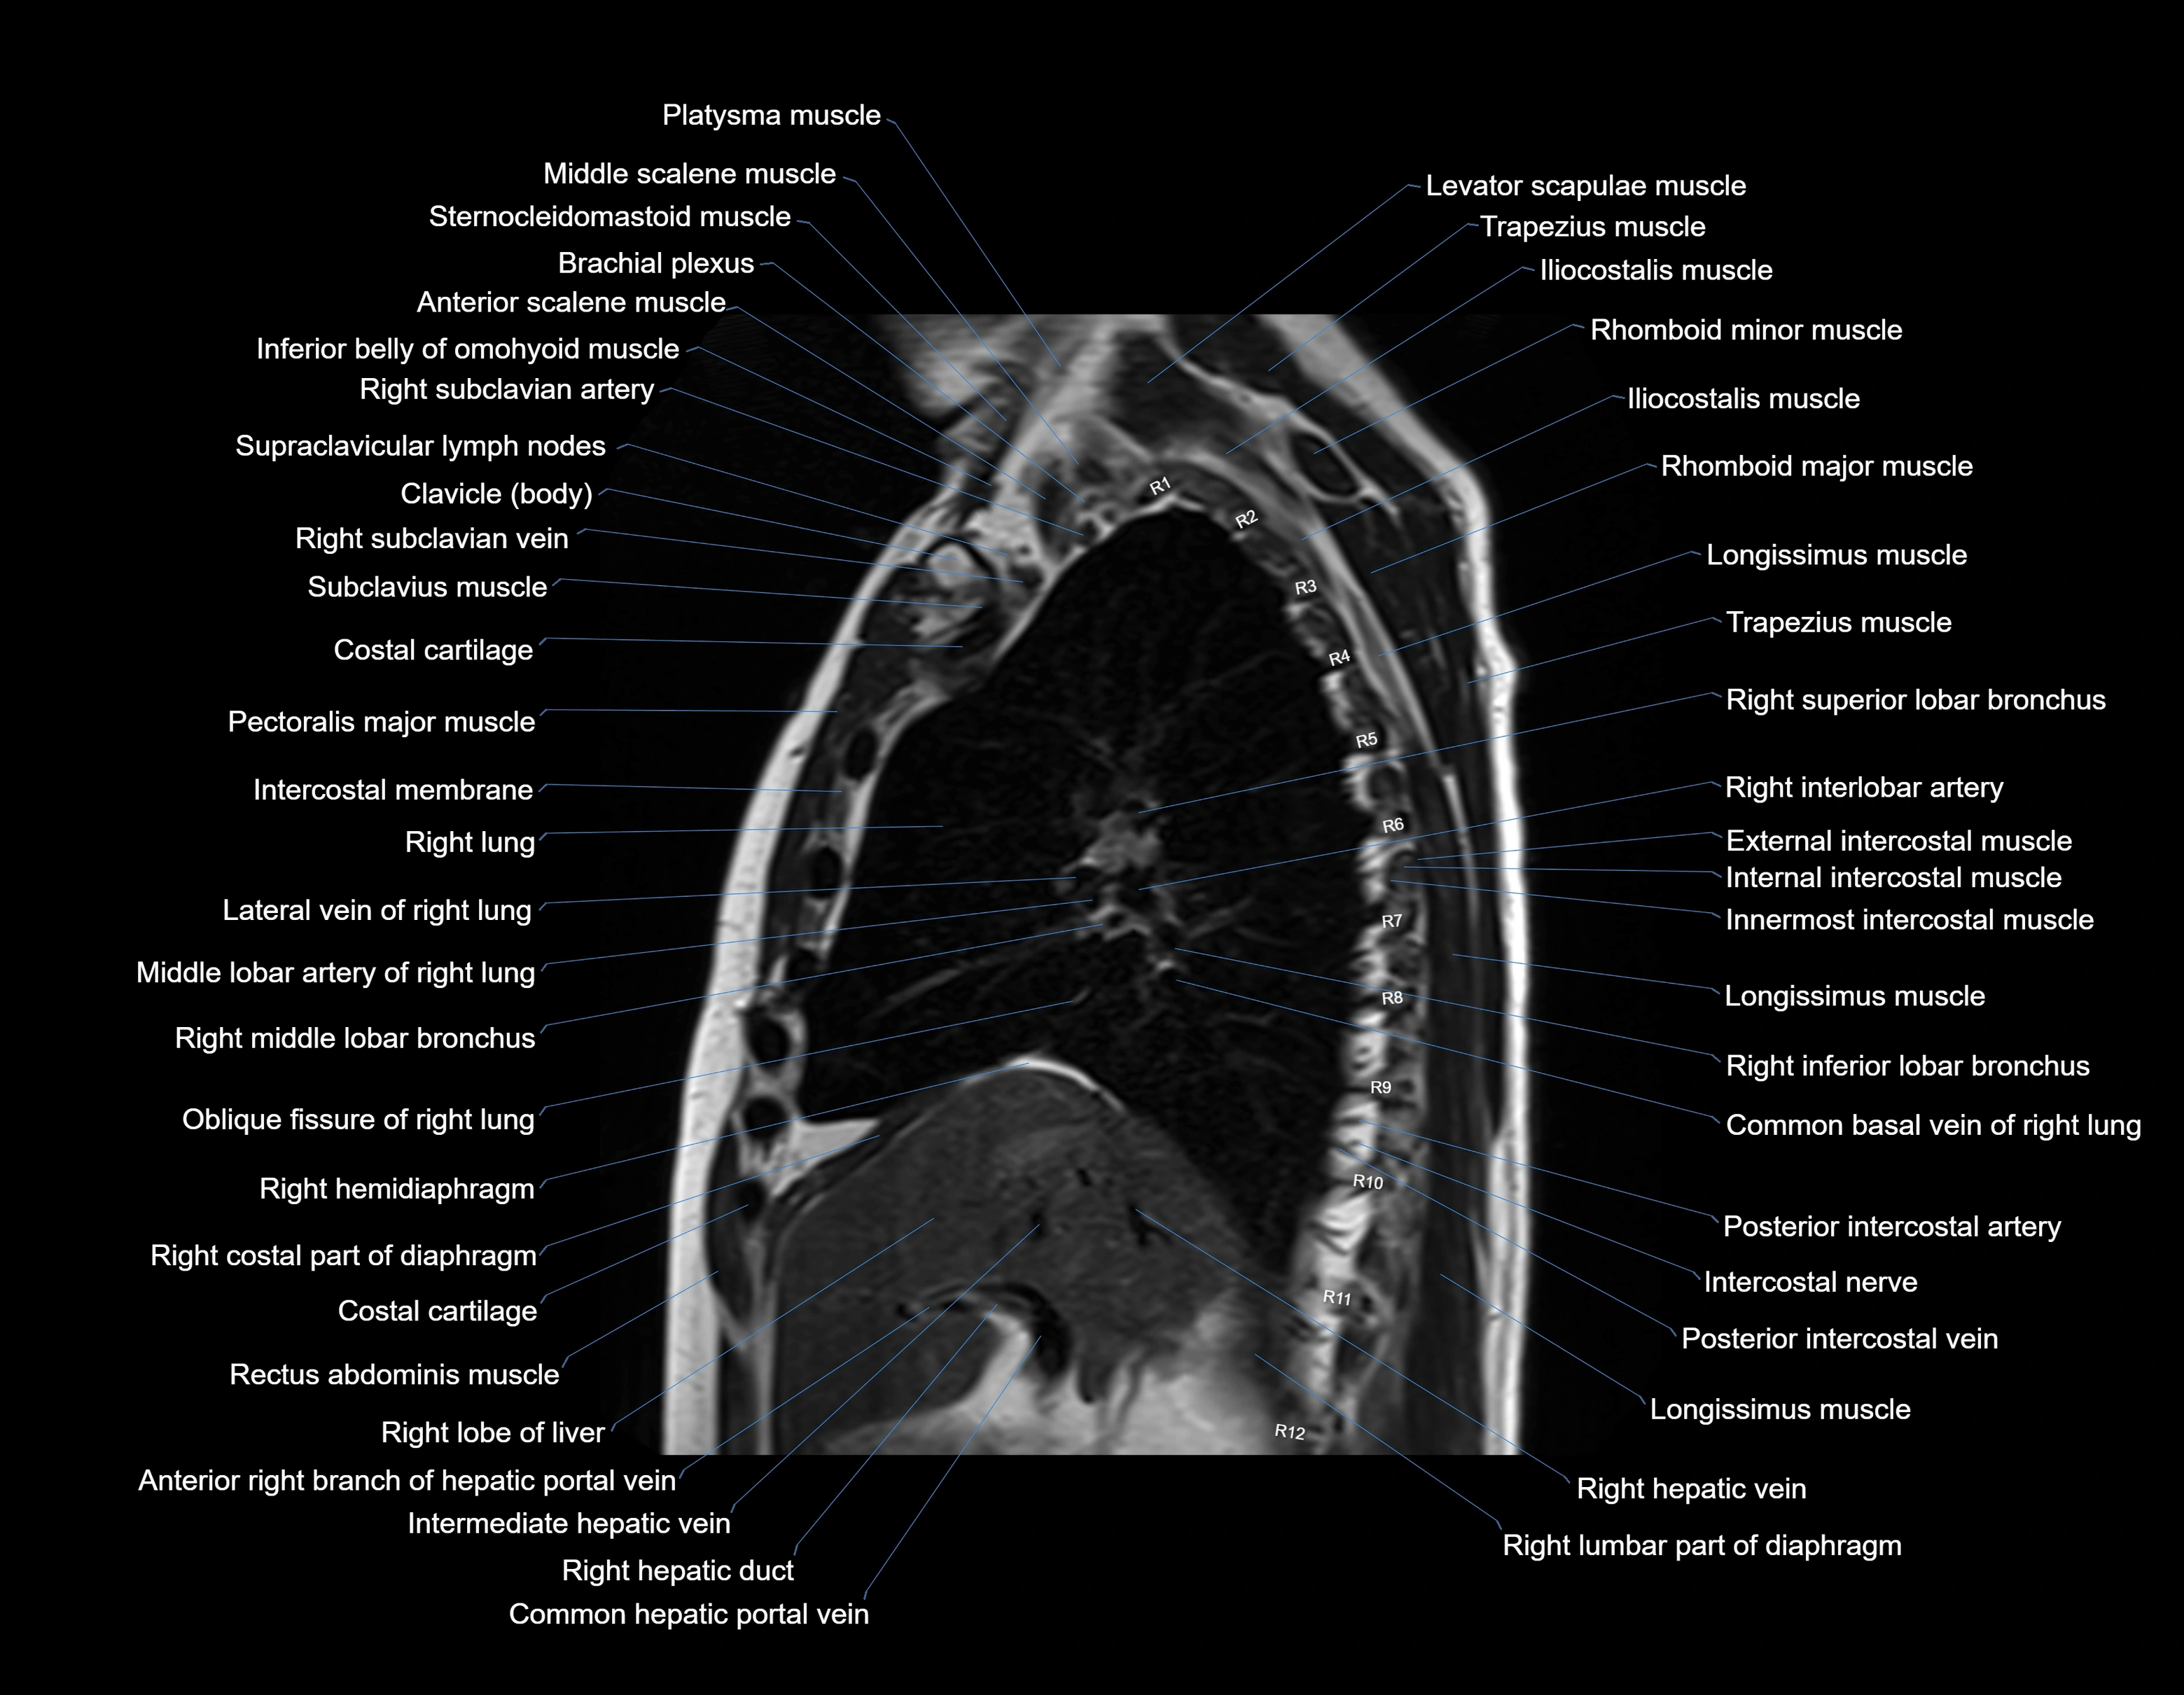

MRI images